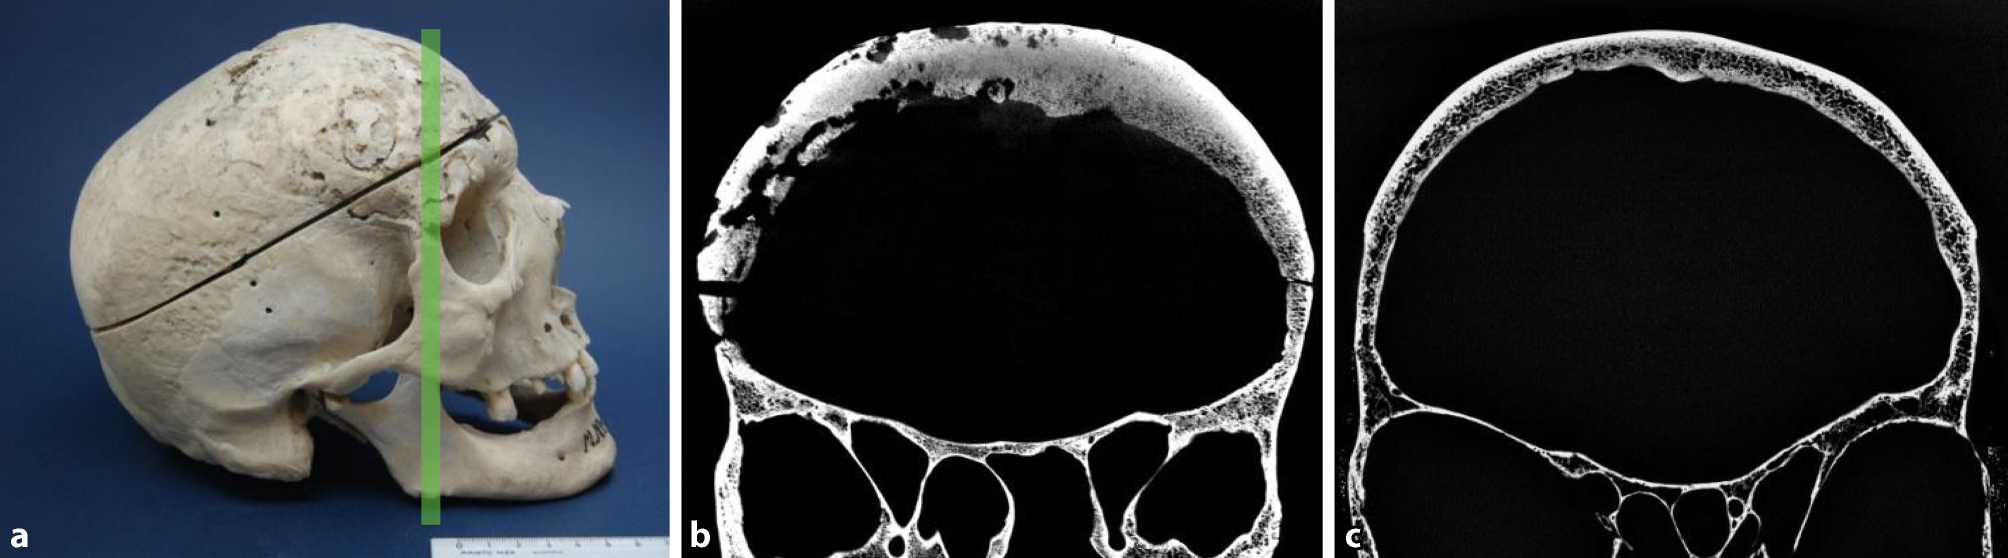

Fig. 4

Cortical loss. Skull of a 69-year-old male diagnosed with syphilis and a 69-year-old male skull bone without syphilitic signs, used as a control. a Lateral view of the syphilitic skull. The green line again indicates the plane of the scan. b µ-CT scan of the syphilitic skull bone showing massive cortical loss compared to the compact cortical bone in Fig. 3c. c Skull of a 69-year-old man used as control without any signs of cortical bone loss

Cortical loss appeared in 80% of infected cases (Table 2). Fig. 4 shows the high level of cortical loss in a skull of a 40-year-old man in comparison to that of a 69-year-old healthy male. Loss of one table was present in over 80% of the 16 specimens, while the skull of 2 males and 1 female showed loss of both the internal and the external tables. Interestingly, in about 75% of the 12 skulls that were affected by the loss of one cortical layer, the internal table was affected. A loss of the external table was found to be present only in one male and two females.